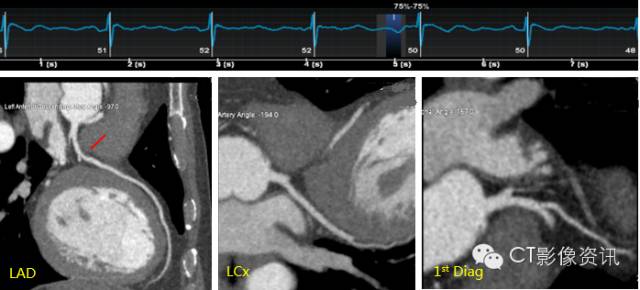

Case 1 女性,74岁,心悸加剧1周。

扫描协议 探测器宽度:140mm, Axial; 管电压和管电流:70kV, Smart mA; 旋转速度:0.28s/rot;迭代:ASiR-V 50%;体重指数:20; 对比剂:270mgI/ml, 30ml, 4.0ml/s; 扫描剂量 :0.2mSv。

CCTA所见 LAD中段钙化斑块、LCX中段狭窄>60%、软斑块。

点评 Revolution CT有70kV、80kV、100kV、120kV及140kV多种电压选择,结合Smart mA可以实现低或超低剂量扫描。ASiR-V技术使低剂量下的图像质量得以保障。